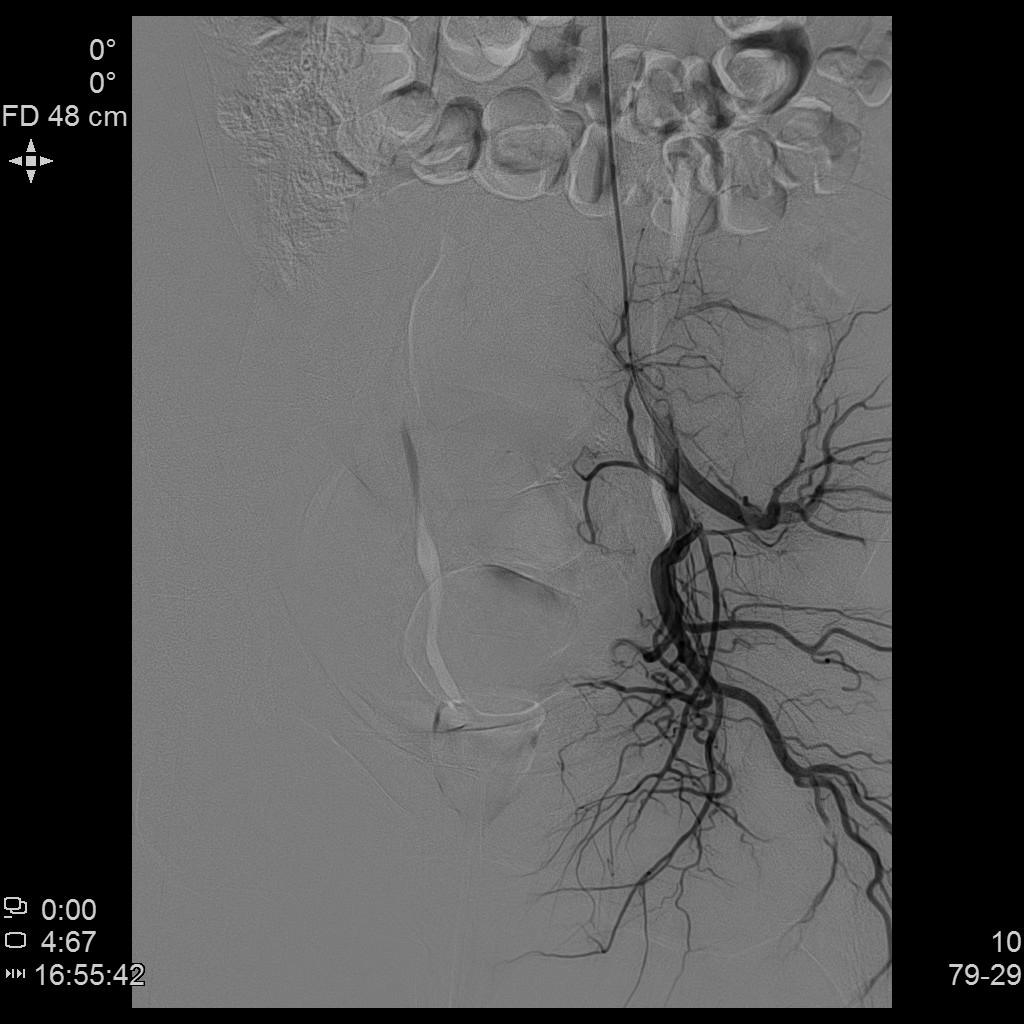

- 经桡动脉入路置入导管造影显示双侧子宫动脉明显增粗,染色丰富,子宫明显增大

- 进一步超选插管右侧子宫动脉造影确认位置

- 微导管进一步超选插管右侧子宫动脉主干造影确认位置

- 栓塞术后复查造影显示右侧子宫动脉分支末梢未见显示

- 进一步超选插管左侧子宫动脉造影确认位置

- 微导管进一步超选插管左侧子宫动脉主干造影确认位置

- 栓塞术后复查造影显示左侧子宫动脉分支末梢未见显示